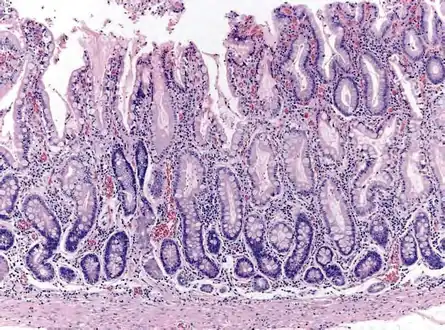

Atrophic gastritis is a process of chronic inflammation of the gastric mucosa of the stomach, leading to a loss of gastric glandular cells and their eventual replacement by intestinal and fibrous tissues. As a result, the stomach's secretion of essential substances such as hydrochloric acid, pepsin, and intrinsic factor is impaired, leading to digestive problems. The most common are vitamin B12 deficiency possibly leading to pernicious anemia; and malabsorption of iron, leading to iron deficiency anaemia.[2] It can be caused by persistent infection with Helicobacter pylori, or can be autoimmune in origin. Those with autoimmune atrophic gastritis (Type A gastritis) are statistically more likely to develop gastric carcinoma, Hashimoto's thyroiditis, and achlorhydria.

Pathophysiology

Autoimmune metaplastic atrophic gastritis (AMAG) is an inherited form of atrophic gastritis characterized by an immune response directed toward parietal cells and intrinsic factor.[6] The presence of serum antibodies to parietal cells and to intrinsic factor are characteristic findings. The autoimmune response subsequently leads to the destruction of parietal cells, which leads to profound Achlorhydria (and elevated gastrin levels). The inadequate production of intrinsic factor also leads to vitamin B12 malabsorption and pernicious anemia. AMAG is typically confined to the gastric body and fundus.